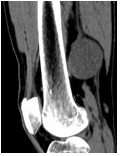

Figure 4: CT showing soft tissue attenuating lesion in the posterior aspect of the lower thigh

A left thigh CT examination (AQUILON GE VOLUSON 16 slice CT machine) showed a soft tissue attenuating lesion which was well-defined, ovoid and size measuring 5.9 x 4.8 x 5.6 cm in the posterior aspect of lower thigh. No intralesional calcifications were noted (Figure 4). There was no extension of the skin, subcutaneous plane, muscular plane and involvement of the bones. Contrast CT study showed homogenous enhancement (Figure 5).

Figure 5: Contrast CT study showing homogenous enhancement